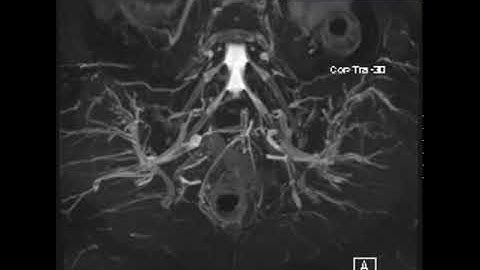

MRI Lumbar plexus and processing on Philips read description